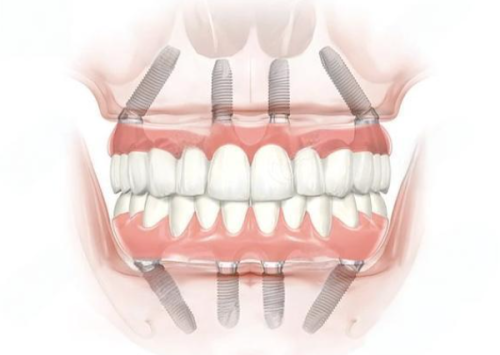

牙齿种植能用多久是许多想要进行牙齿种植的患者非常关心的问题。毕竟,谁都希望种上的牙齿能使用得长久一些。其实,种植牙的使用寿命受多种因素影响,比如材质、个人护理、口腔健康状况和生活习惯等。了解这些因素以及相应的护理秘诀,能帮助大家更好地维护种植牙,延长其使用寿命。接下来,就让我们一起深入揭秘牙齿种植的持久性和护理秘诀吧。

牙齿种植能用多久呢?这并没有一个确切的答案。不过,如果维护得当,种植牙通常可以使用10年至数十年不等。在临床上,有不少患者的种植牙使用了二三十年依然状况良好。但也有部分患者由于各种原因,种植牙在使用几年后就出现了问题。所以,要想让种植牙陪伴我们更久,就需要了解影响其寿命的因素,并做好相应的护理。